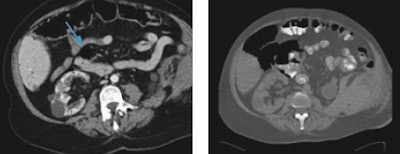

Because the population is aging, general radiologists are likely to come across geriatric trauma in regular routine practice. In the recent past, geriatric patients were often "underimaged," and the severity of injuries was likewise underestimated. Older people don't always complain even when they are in significant pain, explain trauma experts. Furthermore, mechanisms that would cause bruising in younger healthy adults, such as falling from a chair or from standing, can cause fractures and dislocations in geriatric patients.

"We must bear in mind that seemingly minor mechanisms may result in major injury, therefore we should have a low imaging threshold for whole-body CT in the elderly," said Dr. Elizabeth Dick, consultant radiologist and lead for emergency radiology at London's Imperial College NHS Trust. "Trauma teams should avoid piecemeal CT, focusing solely on the injured area. If the patient is stable, a whole-body CT should be performed whenever there is suspicion of significant injury, and don't delay."

"We often find numerous fractures from seemingly minor accidents. Despite a high scan rate in older patients, false-positive rates are low," noted Dick, who is also president of the British Society of Emergency Radiology.

Besides maintaining a high index of suspicion in elderly trauma patients, a deep knowledge of their injuries and syndromes can help radiologists avoid errors: There may be degenerative changes in the spine, such as central cord syndrome (CCS), bruising of the cord caused by compression of the canal space, usually undetectable on CT and requiring MRI.